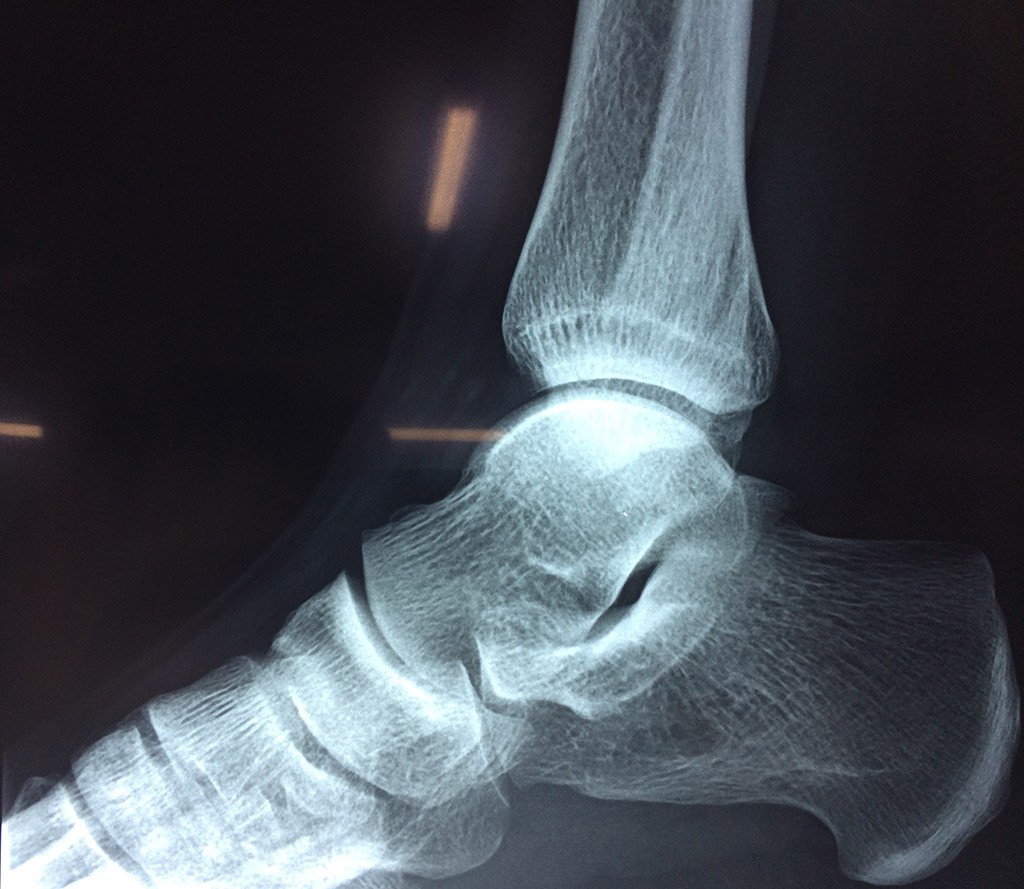

Una fractura de tobillo es la rotura de uno o más de los huesos del tobillo. Estas fracturas pueden ser:

Algunas fracturas de tobillo pueden requerir cirugía si:

- Los extremos de los huesos están desalineados entre sí (desplazados).

- La fractura se extiende hasta la articulación del tobillo (fractura intra-articular).

- Los tendones o ligamentos (tejidos que sujetan los músculos y los huesos entre sí) están rotos.

- El médico cree que sus huesos probablemente no sanen apropiadamente sin cirugía.

- El médico considera que la cirugía puede permitirle una recuperación más rápida y confiable.

- En los niños, la fractura involucra la parte del hueso del tobillo donde el hueso está creciendo.

Cuando se necesita cirugía, es probable que esta implique el uso de clavijas de metal, tornillos o placas para sostener los huesos en su lugar mientras la fractura se consolida. Los elementos de soporte pueden ser temporales o permanentes.